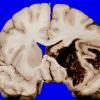

NEOPLASMS (HEMATOLYMPHOID)

Granulocytic Sarcoma (2)